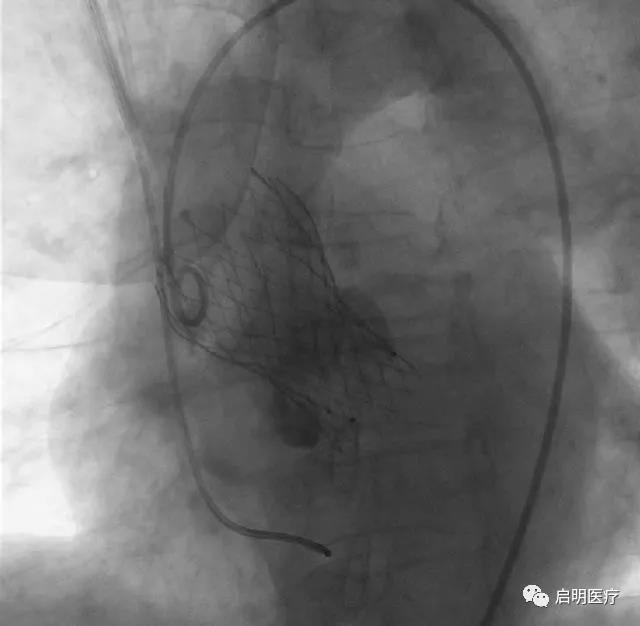

患者,76歲女性,診斷為:主動脈瓣重度狹窄,外科手術(shù)高危(STS 13.8%)。經(jīng)浙醫(yī)二院心臟團(tuán)隊(duì)討論,該患者的解剖結(jié)構(gòu)特點(diǎn)為二葉式主動脈瓣畸形、鈣化不對稱,瓣膜植入過程中移位的可能性大,手術(shù)難度高,適用于可回收系統(tǒng)。

可回收系統(tǒng)允許瓣膜在釋放后收回重新定位,可避免瓣膜植入位置不佳及型號偏差引起的不良事件,如:瓣膜移位、重度瓣周漏、影響二尖瓣工作、壓迫傳導(dǎo)束造成高度房室傳導(dǎo)阻滯等,同時(shí)也降低了手術(shù)的難度,有利于TAVR技術(shù)的推廣和應(yīng)用。

“浙醫(yī)二院的醫(yī)生團(tuán)隊(duì)、浙江省高新企業(yè)瓣膜研究院和啟明醫(yī)療的工程師團(tuán)隊(duì),從VenusA-Valve開始,持續(xù)地進(jìn)行產(chǎn)學(xué)研醫(yī)的緊密合作,到今天,成功地進(jìn)行了中國第一個(gè)可回收瓣膜VenusA Plus的首例臨床應(yīng)用。該產(chǎn)品為新一代介入瓣膜系統(tǒng),釋放、回收穩(wěn)定,操控性和通過性良好,臨床應(yīng)用前景令人期待?!闭汜t(yī)二院王建安教授高度肯定了新產(chǎn)品的臨床價(jià)值。